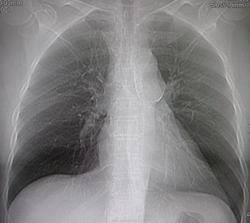

Женщина средних лет. Жалобы на боли в груди, не типичные для ИБС. Когда-то была автодорожная травма, переломы, черепно-мозговая травма. Извините, что топограммы, но снимков у меня нет.

Перво - наперво, выскажусть по поводу, по всей видимости, посттравматической деформации грудины.

Нисходящая часть грудной аорты внушает смутные подозрения

Возможно, и в области дуги имеет место быть аневризма, с обызвествлением стенки.

Была выполнена ангиография, выявлена аневризма. И для планирования стентирования заказана КТ-аортография.